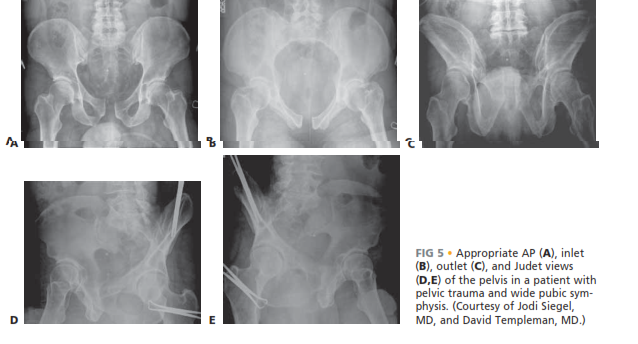

Radiographic evaluation forms the cornerstone of preoperative planning. The standard trauma series includes an anteroposterior (AP) view of the pelvis, supplemented by inlet and outlet views to assess the true rotational and vertical displacement of the pelvic ring. Judet views may be added if concomitant acetabular fractures are suspected.

Image

A high-resolution CT scan of the pelvis with 2D and 3D reconstructions is indispensable. The CT scan allows for a granular evaluation of the posterior sacroiliac joints, sacral fractures, and the exact morphology of the pubic rami. For patients with suspected chronic instability (such as late postpartum presentations), single-leg stance radiographs (flamingo views) can dynamically demonstrate symphyseal translation and confirm the diagnosis. Preoperative templating involves selecting the appropriate multi-hole reconstruction plate and anticipating the degree of contouring required based on the patient's sex and native pelvic morphology as seen on the 3D CT reconstructions.